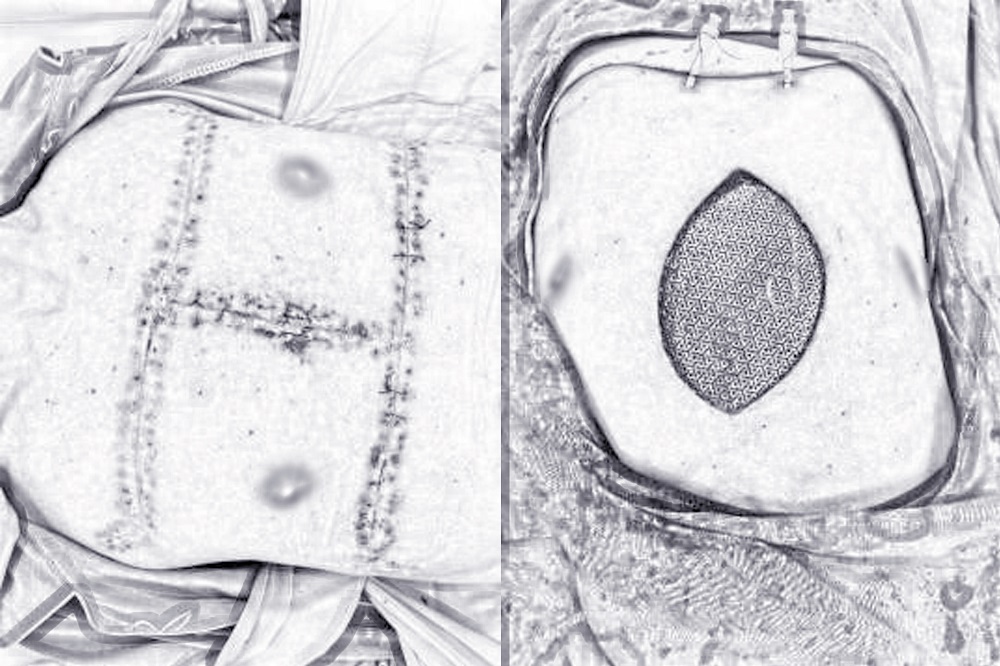

手术过程中,肿瘤完整切除后术后病理报告显示符合高分化软骨肉瘤,术中冰冻病理证实切缘阴性,李航团队随即应用颅骨钛网重建骨性胸壁,测量缺损面积(16*15厘米),钢丝固定,人工型游离双侧筋膜皮瓣,注意保护皮瓣血运,推移缝合后,皮瓣颜色正常,加压包扎,右侧胸腔及创口内置入负压引流。手术过程顺利,患者术后两周康复出院。